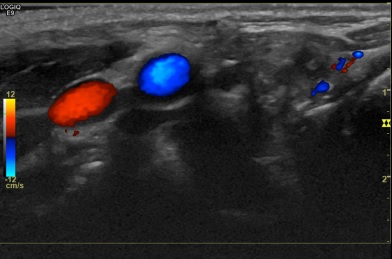

상기환자 외부건강검진이상소견으로 세침검사위해 내원하신 40대중반 여성분으로

의심스러운 갑상선 좌엽 결절 세포검사 진행후 갑상선암으로 진단되었습니다